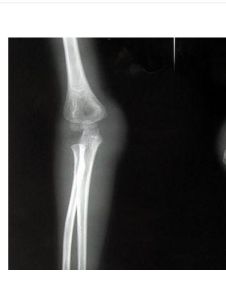

X線檢查:前臂正、側位片可以確診。應包括肘關節以免漏診,注意肱橈關節的解剖關係,必要時可拍健側X線片作對照。凡尺骨上段骨折、而X線片未見到橈骨頭脫位時,應注意除外是否為橈骨頭脫位後自行復位。

根據患者有明顯外傷史,患肢疼痛,活動受限,局限性壓痛。Х線片可確定骨折部位及移位情況。X線攝片顯示在尺骨 1/3交界處,橫形或短斜形骨折多無嚴重粉碎。如尺骨骨折移位明顯,橈骨小頭將完全脫位。在前後位X線攝片、尺側位片可見橈骨頭脫位。